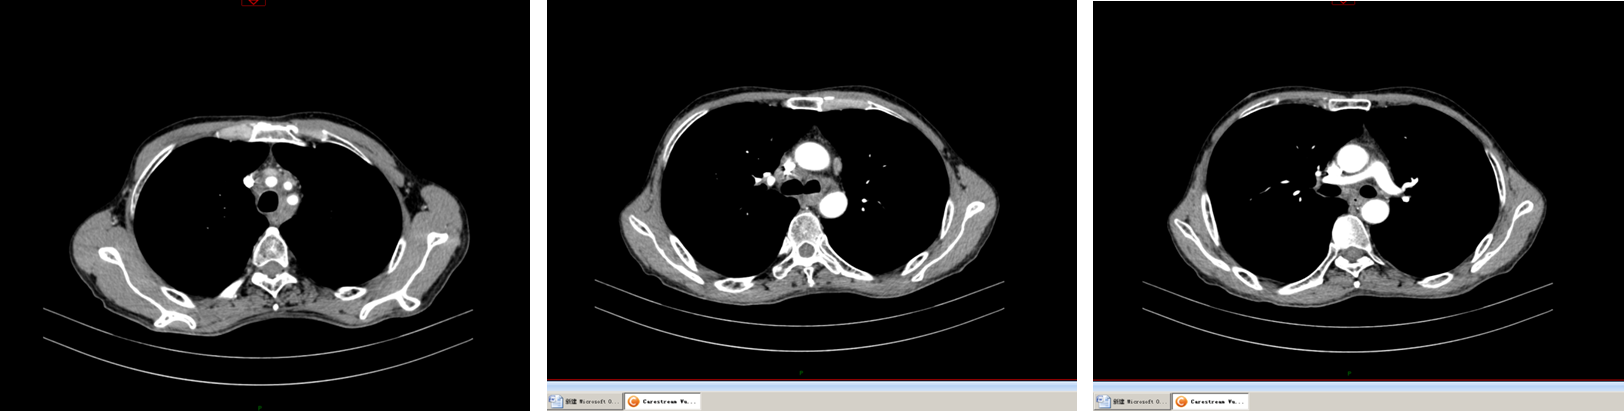

2018年8月7日因进食梗阻感复查CT示:纵隔内淋巴结明显增多增大,较大者截面径约4.0cm×3.3cm,考虑转移。再次分期rⅣ期(纵隔淋巴结转移)。2018年8月—11月行一线GP方案4周期。2018年11月26日予以纵隔转移灶放疗50Gy/25F,期间同步顺铂化疗4次,每次40mg/㎡,因患者治疗期间出现Ⅳ度血小板减少、Ⅱ度白细胞减少,放疗完成23次。治疗后疗效评价PR。患者回当地医院行营养支持及对症治疗。

image005.png

图2 一线行4个周期GP化疗后胸部CT